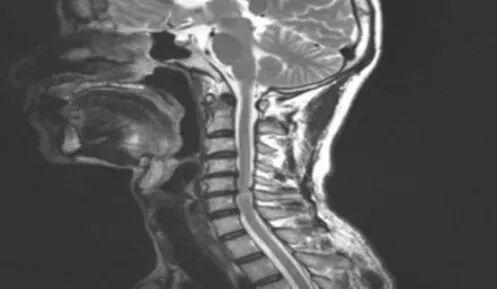

颈椎病为什么会头晕?是压迫血管了么?

颈椎病又称颈椎综合征,是颈椎骨关节炎、增生性颈椎炎、颈神经根综合征、颈椎间盘脱出症的总称,是一种以退行性病理改变为基础的疾患。主要由于颈椎长期劳损、骨质增生,或椎间盘脱出、韧带增厚,致使颈椎脊髓、神经根或椎动脉受压,出现一系列功能障碍的临床综合征。表现为椎节失稳、松动;髓核突出或脱出;骨刺形成;韧带肥厚和继发的椎管狭窄等,刺激或压迫了邻近的神经根、脊髓、椎动脉及颈部交感神经等组织,引起一系列症状和体征。

颈椎病可分为:颈型颈椎病、神经根型颈椎病、脊髓型颈椎病、椎动脉型颈椎病、交感神经型颈椎病、食管压迫型颈椎病。